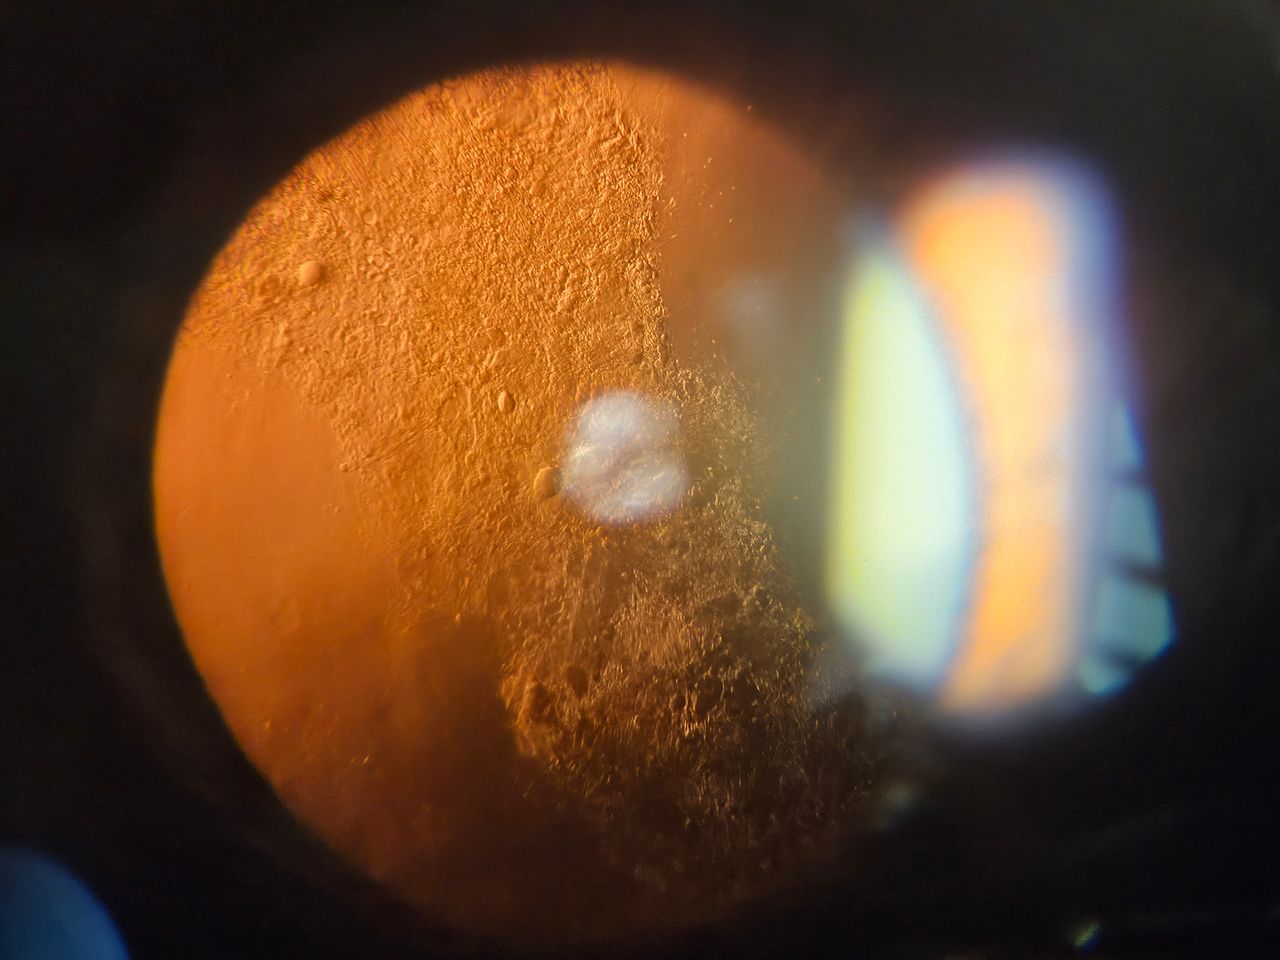

¡Hola! Soy Francisco Ventura, cirujano oftalmólogo apasionado de la cirugía de catarata. Me gusta ser detallista y minucioso. En especial me importa asegurar un buen resultado ANTES de que el paciente entre en el quirófano. Por esa razón me dedico al cálculo complejo de lente intraocular (lente que se coloca después de eliminar la catarata) en pacientes con características complejas ó graduaciones muy grandes.

Diversos Estudios Oftalmológicos disponibles (Tomografía de coherencia óptica, Topografía corneal, Cálculo de lente intraocular, Campimetría visual). Estos se pueden realizar el mismo día de su consulta (con costo adicional, previa confirmación de disponibilidad).

Facoemulsificación de catarata con o sin colocación de lente intraocular

Implante de lente intraocular